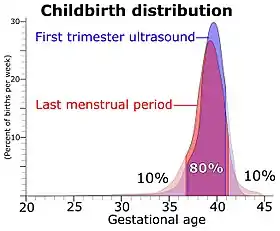

The mean pregnancy length has been estimated to be 283.4 days of gestational age as timed from the first day of the last menstrual period and 280.6 days when retrospectively estimated by obstetric ultrasound measurement of the fetal biparietal diameter (BPD) in the second trimester.[10] Other algorithms take into account other variables, such as whether this is the first or subsequent child, the mother's race, age, length of menstrual cycle, and menstrual regularity. In order to have a standard reference point, the normal pregnancy duration is assumed by medical professionals to be 280 days (or 40 weeks) of gestational age. Furthermore, actual childbirth has only a certain probability of occurring within the limits of the estimated due date. A study of singleton live births came to the result that childbirth has a standard deviation of 14 days when gestational age is estimated by first-trimester ultrasound and 16 days when estimated directly by last menstrual period.[9]